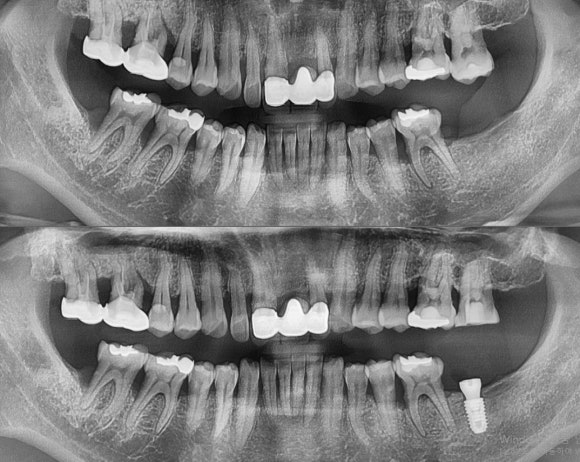

#27 정출 치아 신경치료 & #37 임플란트 식립.

그림 상 오른쪽 아래 치아가 빠진지 오래되어서, 반대편 (#27)치아가 툭 튀어나옴.

대합하는 치아가 없어지면 그 치아를 튀어 오르게 되어있음.

튀어올라서 치아가 흔들리게되면 그 치아도 발치를 해야되는

아깝고도 안타까운 경우가 발생됨.

다행히 #27은 정출이 되었지만 흔들리지 않기 떄문에

위아래 공간 확보를 위해 신경치료 후 보철 치료를 진행해야함

(미리 임플란트를 해서 회복했다면 신경치료 + 보철 값을 아낄수 있었는데.. 그래서 야단침-..-)

#37 임플란트 식립 부위도 치아가 빠진지 오래되어서

뼈의 폭과 높이 양 질이 좋지 않았음.

CT를 찍고 모의수술 후 신경손상을 피하면서 안전하게 들어감.

초기고정도 만족스럽게 됨.

결론 : 치료할건 미루지 말고 미리미리 하는게 좋습니다.